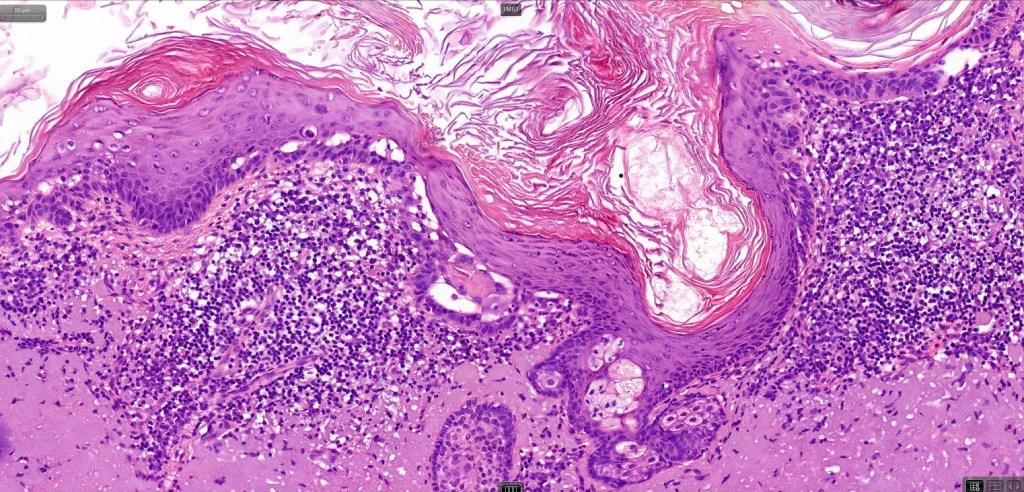

•Hyperkeratotic/hyperplastic actinic keratosis represents the prototype-alternating hyperkeratosis & parakeratosis- the former overlies the follicular & sweat duct ostia (Freudenthal funnel) while the latter overlies the interadnexal dysplastic epithelium & ranges from basal cell layer though to full thickness dysplasia (Bowenoid actinic keratosis); budding from the epidermis is a common finding; dysplastic epithelium commonly forms a mantle around the follicles and superficial sweat ducts

•Variable lack of maturation, nuclear irregularity, pleomorphism & mitotic activity

•Solar elastosis

.Superficial dermal lymphohistiocytic infiltrate